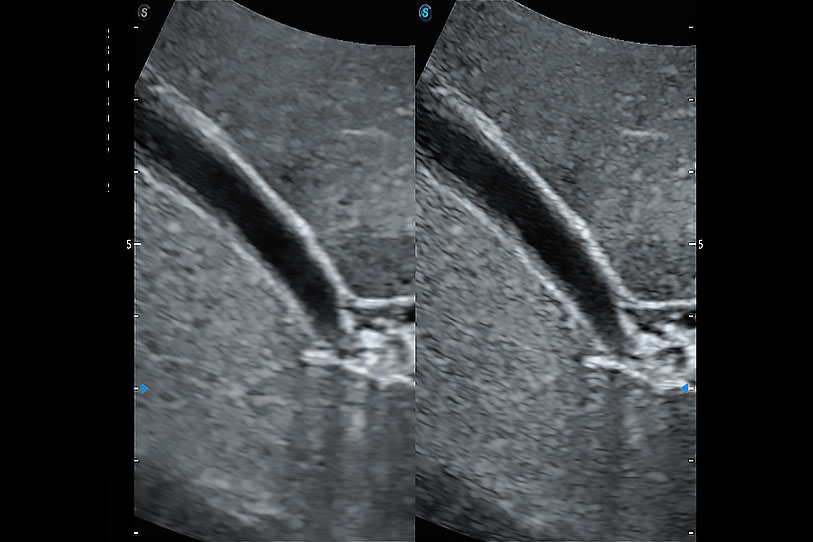

通過色彩血流和實(shí)時(shí)寬景相結(jié)合,可觀察到完整的靜脈或動脈的血流,方便醫(yī)生檢查。實(shí)時(shí)掃查過程中,如有任何操作失誤也可以很容易地進(jìn)行回掃擦除,而不會中斷掃查。